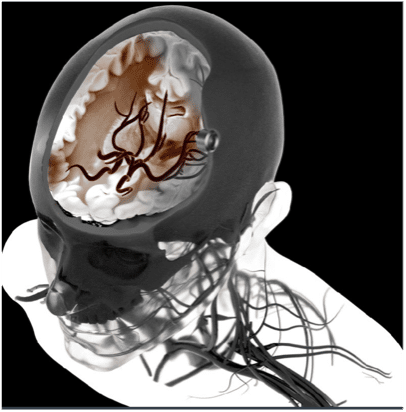

A key challenge in dealing with strokes is distinguishing between ischemic and hemorrhagic stroke as early as possible, as well as monitoring aneurysm. A promising approach to achieve this is transcranial imaging of deep vasculature (and quantification of hemodynamic parameters).

This is now possible in the adult human brain at microscopic resolution using ultrasound localization microscopy (ULM) of intravenously injected microbubbles. To take advantage of this concept, we’re developing a transcranial ULM scanner for stroke and aneurysm diagnosis in adults, in close collaboration with Geneva University and Physics for Medicine Paris.

This is a ‘moonshot’ project that is focused on developing a highly temporally-resolved version of our existing ultrafast localization microscopy (ULM) technology for Iconeus One. In this clinical proof-of-concept project, we are initially aiming to achieve diagnosis and treatment monitoring of cerebral small vessel disease, stroke, aneurysms, and alterations of the neurovascular response.

To reduce the temporal resolution from the current 60 s to the <1 s needed for this ‘functional ULM’ (fULM) technology, we’re planning to use a set of highly sensitive ultrasound probes within a helmet. This will present significant challenges, but in conjunction with our collaborators in the EU-funded MICROVASC project, we’re confident about making progress, and are looking forward to seeing what can be achieved for clinical applications.